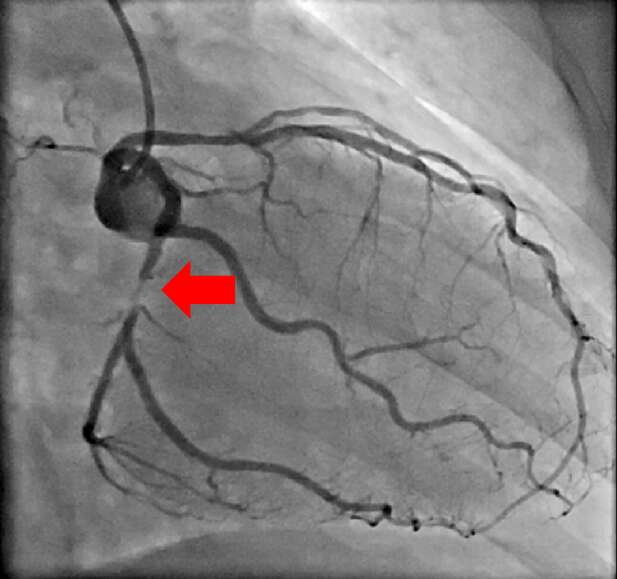

【治療例3:狭心症ステント拡張術】

心臓に栄養を送る血管を冠動脈と呼びますが、冠動脈が狭窄すると心筋梗塞や狭心症を発症します。

冠動脈の狭窄又は閉塞を専用の治療器具を用いて治療していきます。

治療前

赤矢印の冠動脈が狭窄している

治療後

狭窄していた冠動脈にステントを留置し、血流が元に戻っている